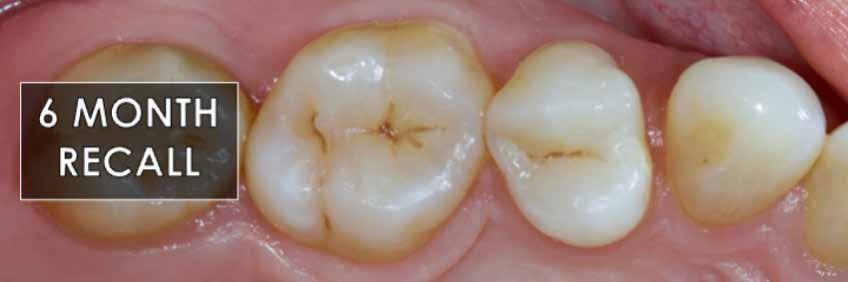

2. ábra: A páciens egy nem megfelelő I. osztályú ezüst-amalgám töméssel és II. osztályú szuvasodással jelentkezett. A fog izolálása kofferdám alkalmazásával történt.

3. ábra: A preparálás, a bondozás és a kompozit felvitele után. (Megjegyzés: némi kompozit túlfolyás látható a mesiális doboz axiális falain).

4. ábra: A durva finírozás után a restauráció pereme sima és anatómiailag is megfelelő.

Klinikai példa az 2–4. képeken látható.

9. ábra: Hat hónapos kontroll.